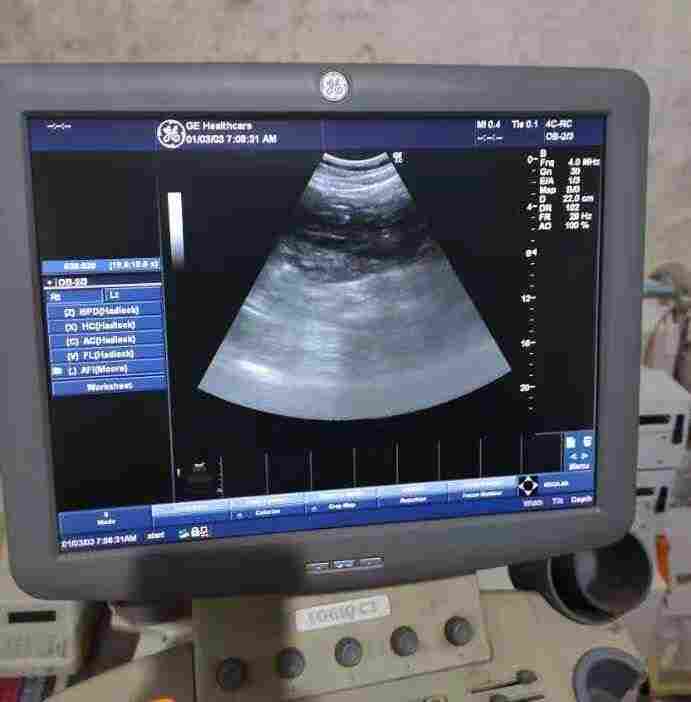

2、彩超探头故障

彩超探头是彩超独有部件,其故障有性,但也不复杂。通常用的彩超探头有线阵探头和机械扇扫探头。其中机械扇扫探头故障较多,常见故障为扇扫探头内有气泡,处理方法是:排气、灌油,在有关书中叙述过处理方法,这里不再重复,另一常见故障是扇扫探头不转,通常是探头本身驱动电机损坏,这时处理比较麻烦,需把探头锯开。

彩超探头价格昂贵,容易损伤,因此需要特别注意探头的保养及维护。 超声诊断仪,如B、M、多普勒系统,在临床上适用范围广,操作简便。超声诊断是目前医院影像诊断中重要手段,但在实际使用中发现,由于维护、保养不及时,致使彩超探头性能下降甚至损坏。影响了超声诊断仪的正常使用,给临床工作造成影响。

彩色多普勒超声诊断仪,由于设备大量采用高新技术,精密度高,所以,成本较昂贵。而探头是这类设备*重要部件,它有双重作用:一是将高频信号转换为超声信号,再将从人体反射回来的回声信号转换为电信号。从整个设备来看,探头要占去整机成本价的1/3到1/5,所以在使用彩超设备时,对探头要倍加保护,定期保养,延长机器使用寿命。

彩超探头日常维护和保养

彩超机探头对于超声系统来说是一个关键部件

它的*根本的工作是实现电能和声能之间的相互转换,即既能把电能转换成声能,又能把声能转换成电能。 完成这一系列转换的关键元素是压电晶体( Piezoelectric crystal )。 同一块晶体被精密地切割成一个一个单元( Element ), 有序地排列成几何阵列。

一个探头可能由少则几十个,多则成千上万个阵元组成。每个阵元由1个到3个单元组成。在使用过程中注意轻拿轻放,避免与其他物品发生碰撞;在插拔探头时,必须要确定探头未处于工作状态或者已经关闭电源。

当彩超探头使用完成后,记得清洁探头声透镜表面耦合剂。可用软布蘸水清洁探头表面;如果探头比较脏,则可先用软布沾清洁液(例如中性肥皂水)清洗,再用软布沾水把清洁液清除干净;清洁完毕,用干净的柔软干布擦干探头。在清洗过程中,探头不能使用酒精或含酒精擦拭物,否则可能会导致探头电缆线或衬套等部件硬化。对超声探头进行消毒时,使用的液体化学消毒剂来进行消毒,如戊二醛溶液,消毒剂溶液。消毒完毕,用无菌水清洗探头上的消毒液,再用已消毒的柔软干布将探头擦干。切记探头的浸泡部分不能过探头外壳侧面的方位标示处,探头浸泡时间不要过1小时。不能使用高温高压进行消毒,会导致探头内部结构损坏。

其次,当探头声透镜出现破损,耦合剂会进入探头内,对其内部的电压晶片产生影响,导致晶片被损坏,因此要注意透镜面的接触物不能具有锋利性,且已破损的声透镜要及时维修。